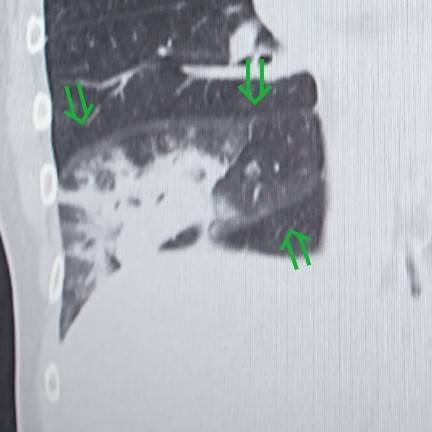

気管支透亮像

こちらも肺炎に特徴的な所見です。

air bronchogram(えあーぶろんこぐらむ)とも言います。

先程の患者さんにも見られますが、もっとわかりやすいのがコチラです。

同じように区域性ですが、左右両肺とも広い範囲で炎症を起こしています。

そして炎症の中に気管支が透けて見えています。

これが気管支透亮像です。

木の枝みたいだね。

肺がんの場合は気管支にもどんどん浸潤していくので気管支は途絶してしまいます。